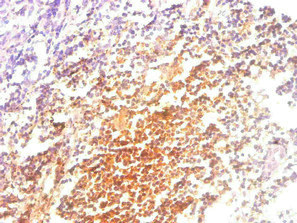

大規(guī)模結(jié)直腸癌基因組研究顯示,MSI-high腫瘤常出現(xiàn)抗原呈遞機器的免疫編輯特征,包括B2M與HLA基因的雙等位基因喪失(含拷貝數(shù)改變與拷貝中性LOH)[18]。臨床隊列進一步報告MSI-H CRC中B2M突變率可達約24%,且突變與蛋白表達缺失高度一致,支持“基因型—表型”的緊密關聯(lián) [19];同時,B2M熱點突變在微衛(wèi)星不穩(wěn)定CRC中富集,且可能在免疫治療前已存在,提示其既可能是早期演化事件,也可能在治療壓力下被選擇 [20]。

在其他腫瘤中,B2M改變與HLA表達降低、CD8+ T細胞浸潤減少等表型共同出現(xiàn),強化了“抗原呈遞受損→免疫逃逸”的解釋框架,例如EBV陽性DLBCL中B2M突變與HLA表達降低及CD8+浸潤減少并存 [21],并與多類EBV相關或血液腫瘤中HLA相關基因頻繁受損的模式一致 [22]。在惡性膠質(zhì)瘤中,針對HLA區(qū)域測序復雜性的研究亦識別出B2M與TAP基因體細胞突變,并提示其在復發(fā)GBM中可能富集,指向進展或治療過程中選擇壓力的作用 [23]。在MSI/dMMR胰腺導管腺癌中,B2M失活可表現(xiàn)出原發(fā)與轉(zhuǎn)移灶間異質(zhì)性,提示治療評估需關注空間差異與轉(zhuǎn)移部位的重要性 [24]。